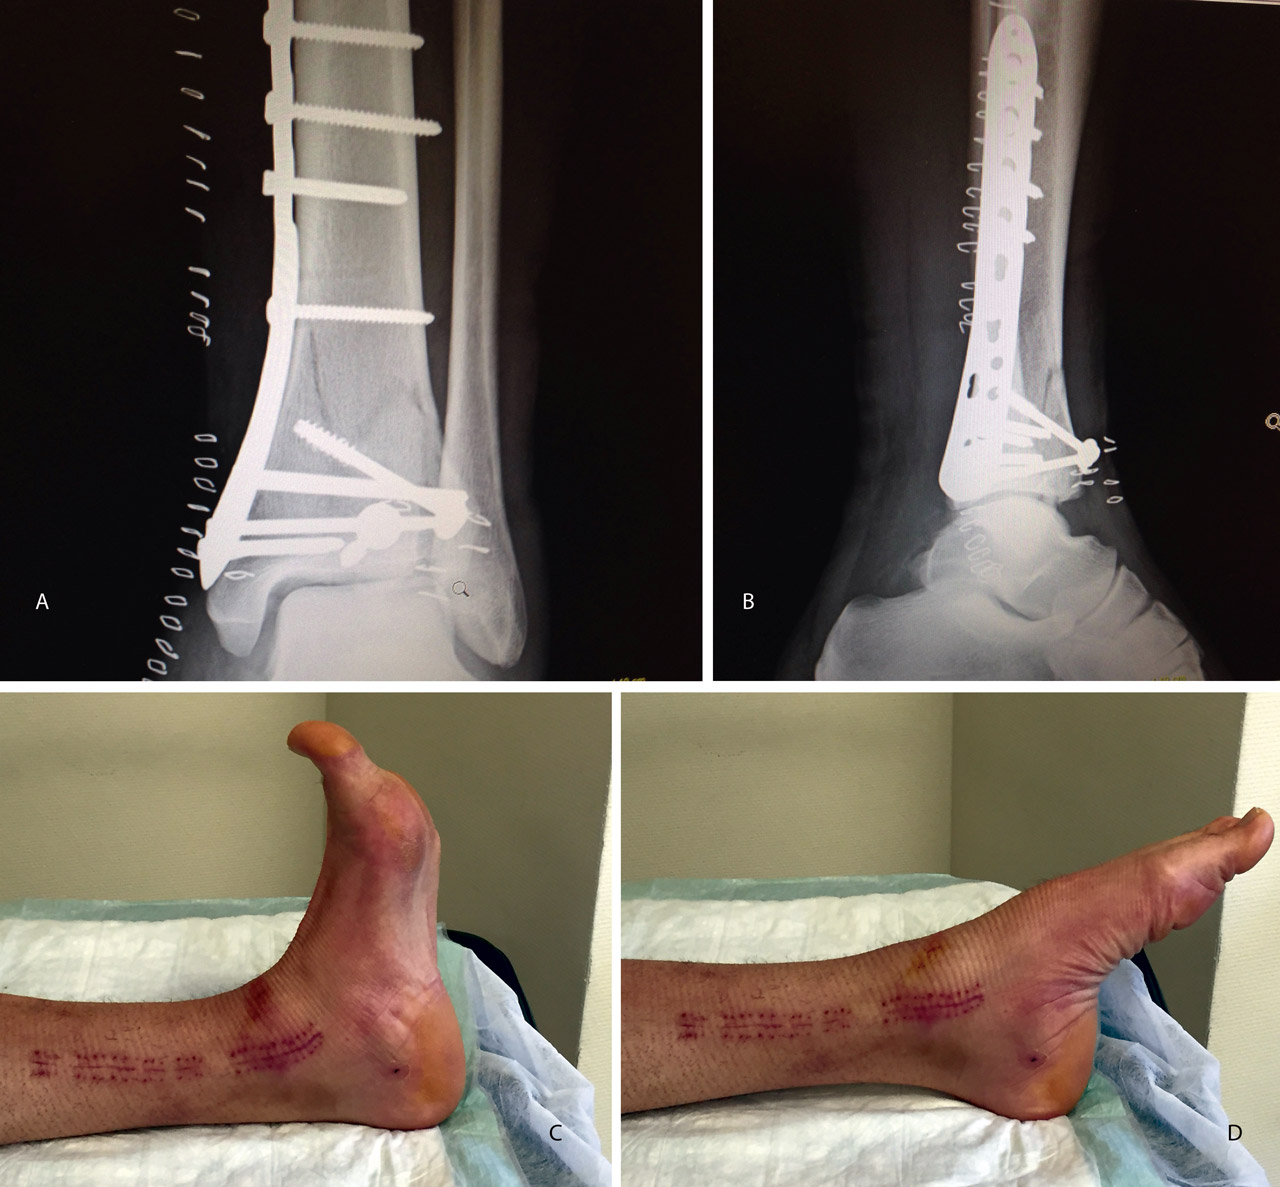

En cuanto al postoperatorio, inmovilizamos al paciente con una férula de yeso hasta las 3 semanas. A partir de ese momento, colocamos una férula de material termoplástico que se puede retirar para movilizar el tobillo, iniciando la carga con una bota ortésica de tipo Walker a las 6-8 semanas (Figuras 6 a 11).

Posteriormente, colocaremos la placa en la tibia por vía MIPO realizando una incisión interna, separando la vena safena y deslizando la placa que se fija de manera provisional. Tras comprobar por radioscopia la buena posición del implante, se realiza la fijación definitiva con los tornillos que consideremos adecuados. En el caso de que tengamos que usar un fijador, este sustituye a la placa interna (Figuras 17 a 20).

Figura 17. Caso 3: fractura tipo C. Radiografías sin tracción y con tracción comprobando la reducción.

Figura 18. La tomografía computarizada muestra los fragmentos principales de la fractura, estando desplazado el Tillaux que se reduce con la tracción.

Figura 19. Colocación del tornillo en el Tillaux con la extremidad en tracción y posteriormente la placa MIPO (minimally invasive plate osteosynthesis).

Figura 20. Radiografías postoperatorias y resultado final con movilidad completa en flexoextensión del tobillo.